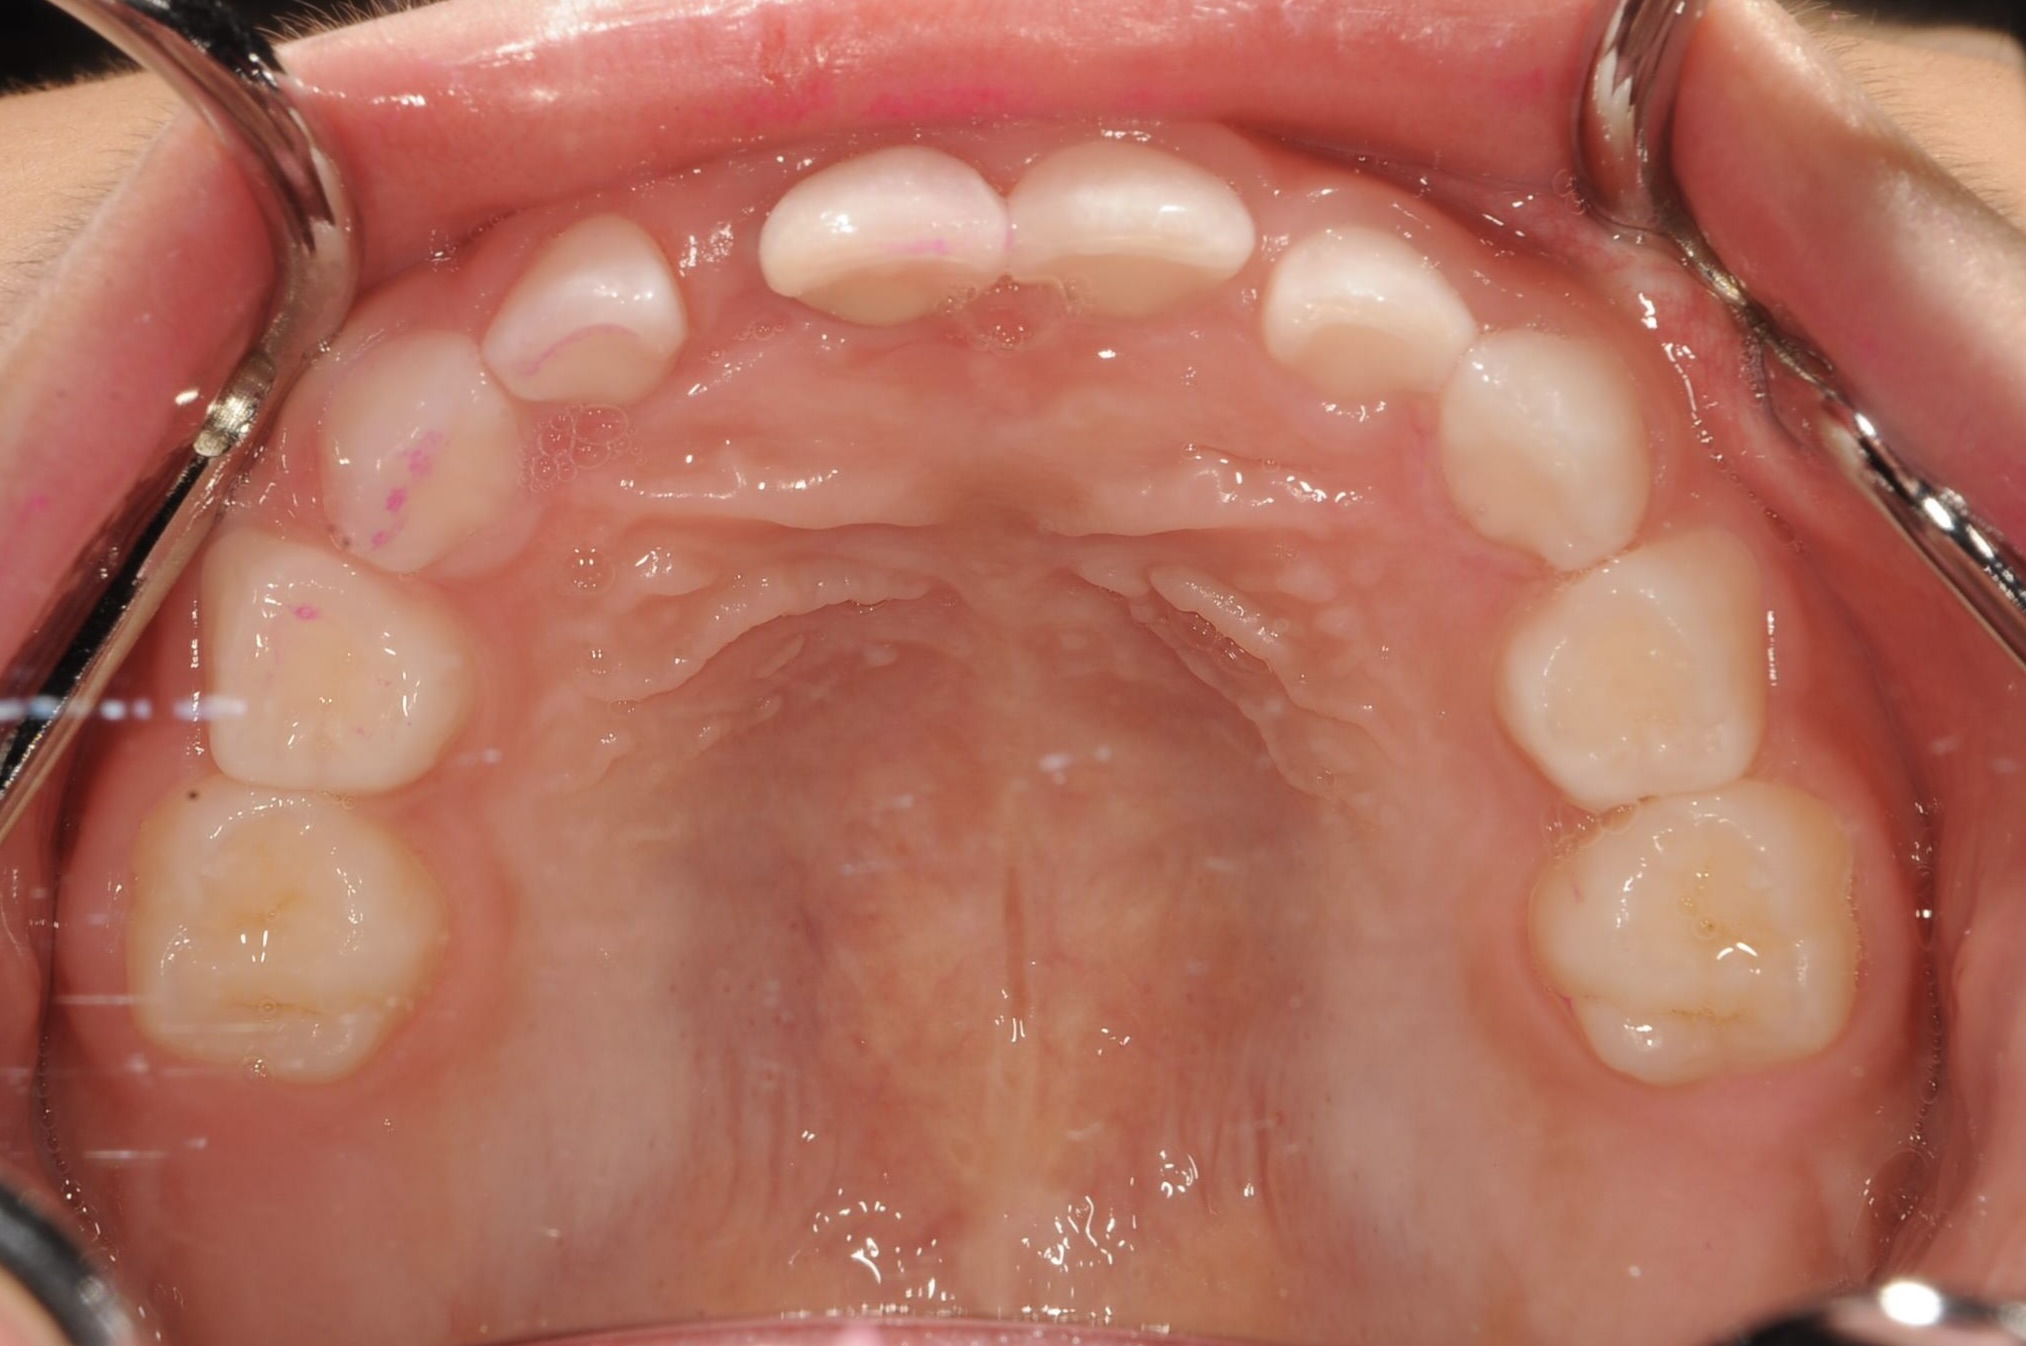

BEFORE

AFTER

治療内容

上下の歯並びの幅を拡げつつ、前歯の関係を改善しました。

使用装置

急速拡大装置

リンガルアーチ

機能的矯正装置(マイオブレース)

抜歯部位

抜歯なし

治療期間

2年 + 後戻り止め期間(5年)

通院回数

25回

費用

50万円程度(税別)